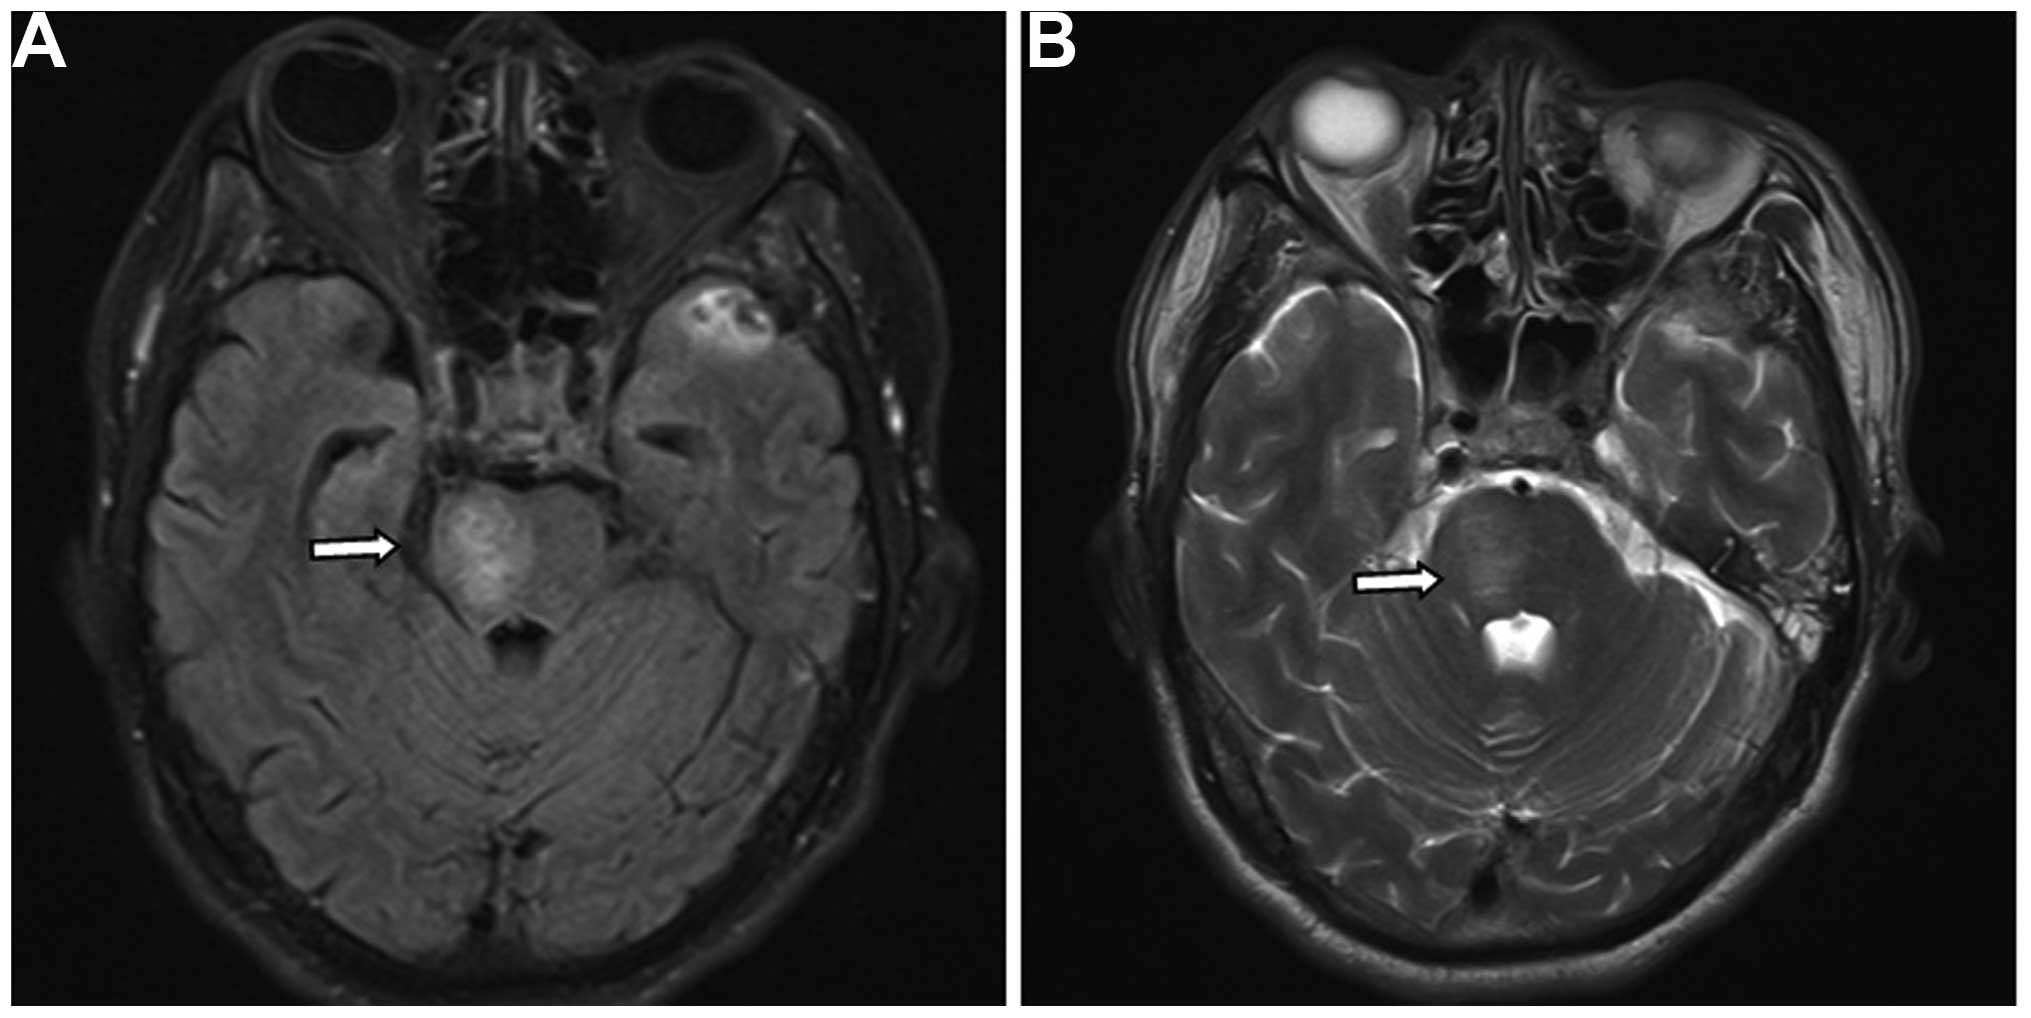

Brainstem edema caused by traumatic carotid-cavernous fistula (TCCF) is rare, and there is little information available regarding its clinical characteristics. The present report describes the case of a 51‑year‑old man with TCCF, who presented with right exophthalmos and intracranial bruit for 1 week. One month prior to admission at hospital, he fractured the frontal and ethmoid sinuses. Digital subtraction angiography confirmed the diagnosis of TCCF, and magnetic resonance imaging (MRI) suggested edema on the right side of the pons. Five days after admission, the patient exhibited left hemiparesis, and MRI revealed aggravation of the brainstem edema. Following treatment with transarterial balloon embolization, the clinical symptoms, including hemiparesis, were relieved; at the 1‑month follow‑up, the brain edema had disappeared. The patient was normal at the 6‑month follow‑up. Following the report of the present case, we reviewed six additional cases previously reported in the literature and discussed the potential mechanisms of TCCF‑associated brainstem edema. We conclude that occlusion of the superior petrosal sinus may contribute to brainstem edema caused by TCCF. Relief of the brainstem edema and brainstem edema‑associated clinical symptoms can be achieved with transarterial coil or balloon embolization of the TCCF to reduce the drainage pressure in the brainstem veins.

Figure 4